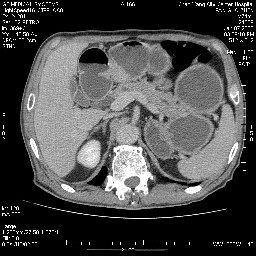

女,74岁,呕吐10余日

还有胃、脾之间可见有侧支循环建立。左肾盂积水。

双肾多发小囊肿;左肾积水。

十二指肠水平段腔内占位伴梗阻,中等度较为均匀的强化,洗脱慢,区域淋巴结显示增多,符合腺癌表现。下腔静脉变异。

今日手术结果:胰腺钩突癌侵犯十二直肠,腹腔淋巴结转移.